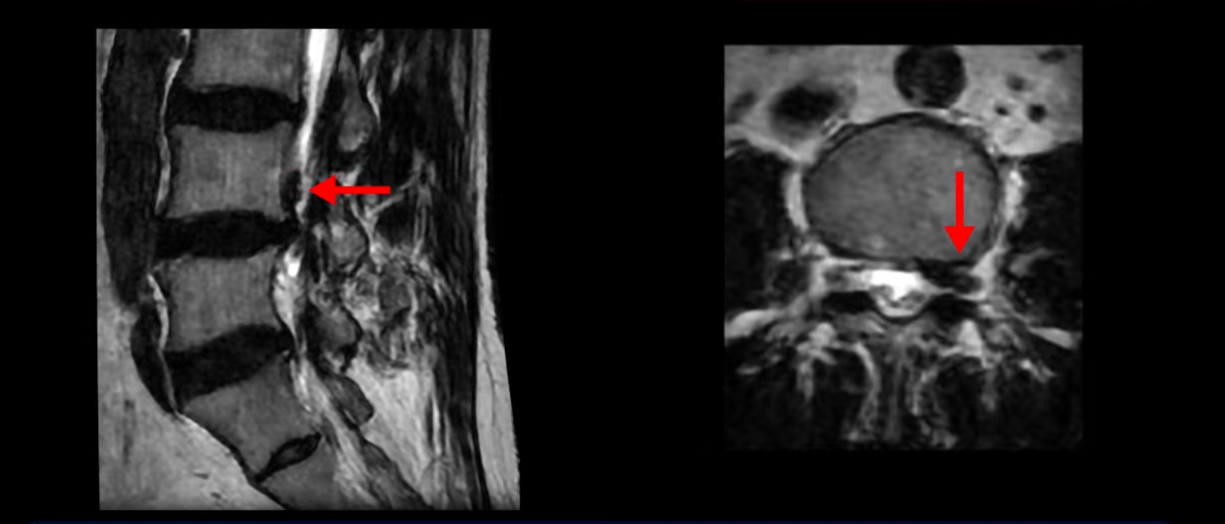

이분은 왼쪽 무릎 아래로 본인 표현으로는 다리를 잘라 버리고 싶다고 할 정도의 심한 통증이 있는데 보통 이런 표현은 디스크 파열이 발생했을 때 많이 사용하는 표현입니다. 이분 4번 5번 디스크를 자세히 보면 왼쪽으로 파열되어 밀려 올라간 디스크 수핵을 볼 수 있습니다.

옆에서도 보이지만 단면에서도 왼쪽으로 심하게 밀려나온 수핵이 잘 보입니다.